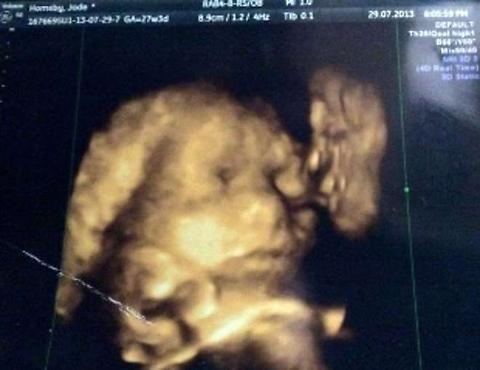

ROMA – Una giovane inglese ventunenne incinta, Jade Hornsby, è andata a fare come da routine, l’ecografia dal medico. Ma quando ha visto l’ecografia è rimasta paralizzata vedendo un gioco di luce e scansioni accanto al feto. Gioco di luce e scansioni che la ragazza ha identificato nella faccia di un uomo intento a baciare la sua bimba.

Non un uomo qualsiasi, ma il nonno defunto. Jade ne è convinta: “Quella è la faccia di mio nonno. È più evidente di quella di mia figlia, ed è davvero inquietante. Vedete? Ci sono le labbra allungate verso la guancia di mia figlia, e poi gli occhi, il naso, il mento. Tutto molto definito”. “Quando mia madre ha visto la scansione – ha raccontato la ragazza al Mirror – è rimasta a bocca aperta e ha detto subito: è lui, è mio padre Jack! E’ come se mio nonno stesse benedicendo la pronipote ancora nel grembo materno. Ed è stato bellissimo pensarlo, da quel momento sento che mia figlia è protetta”.